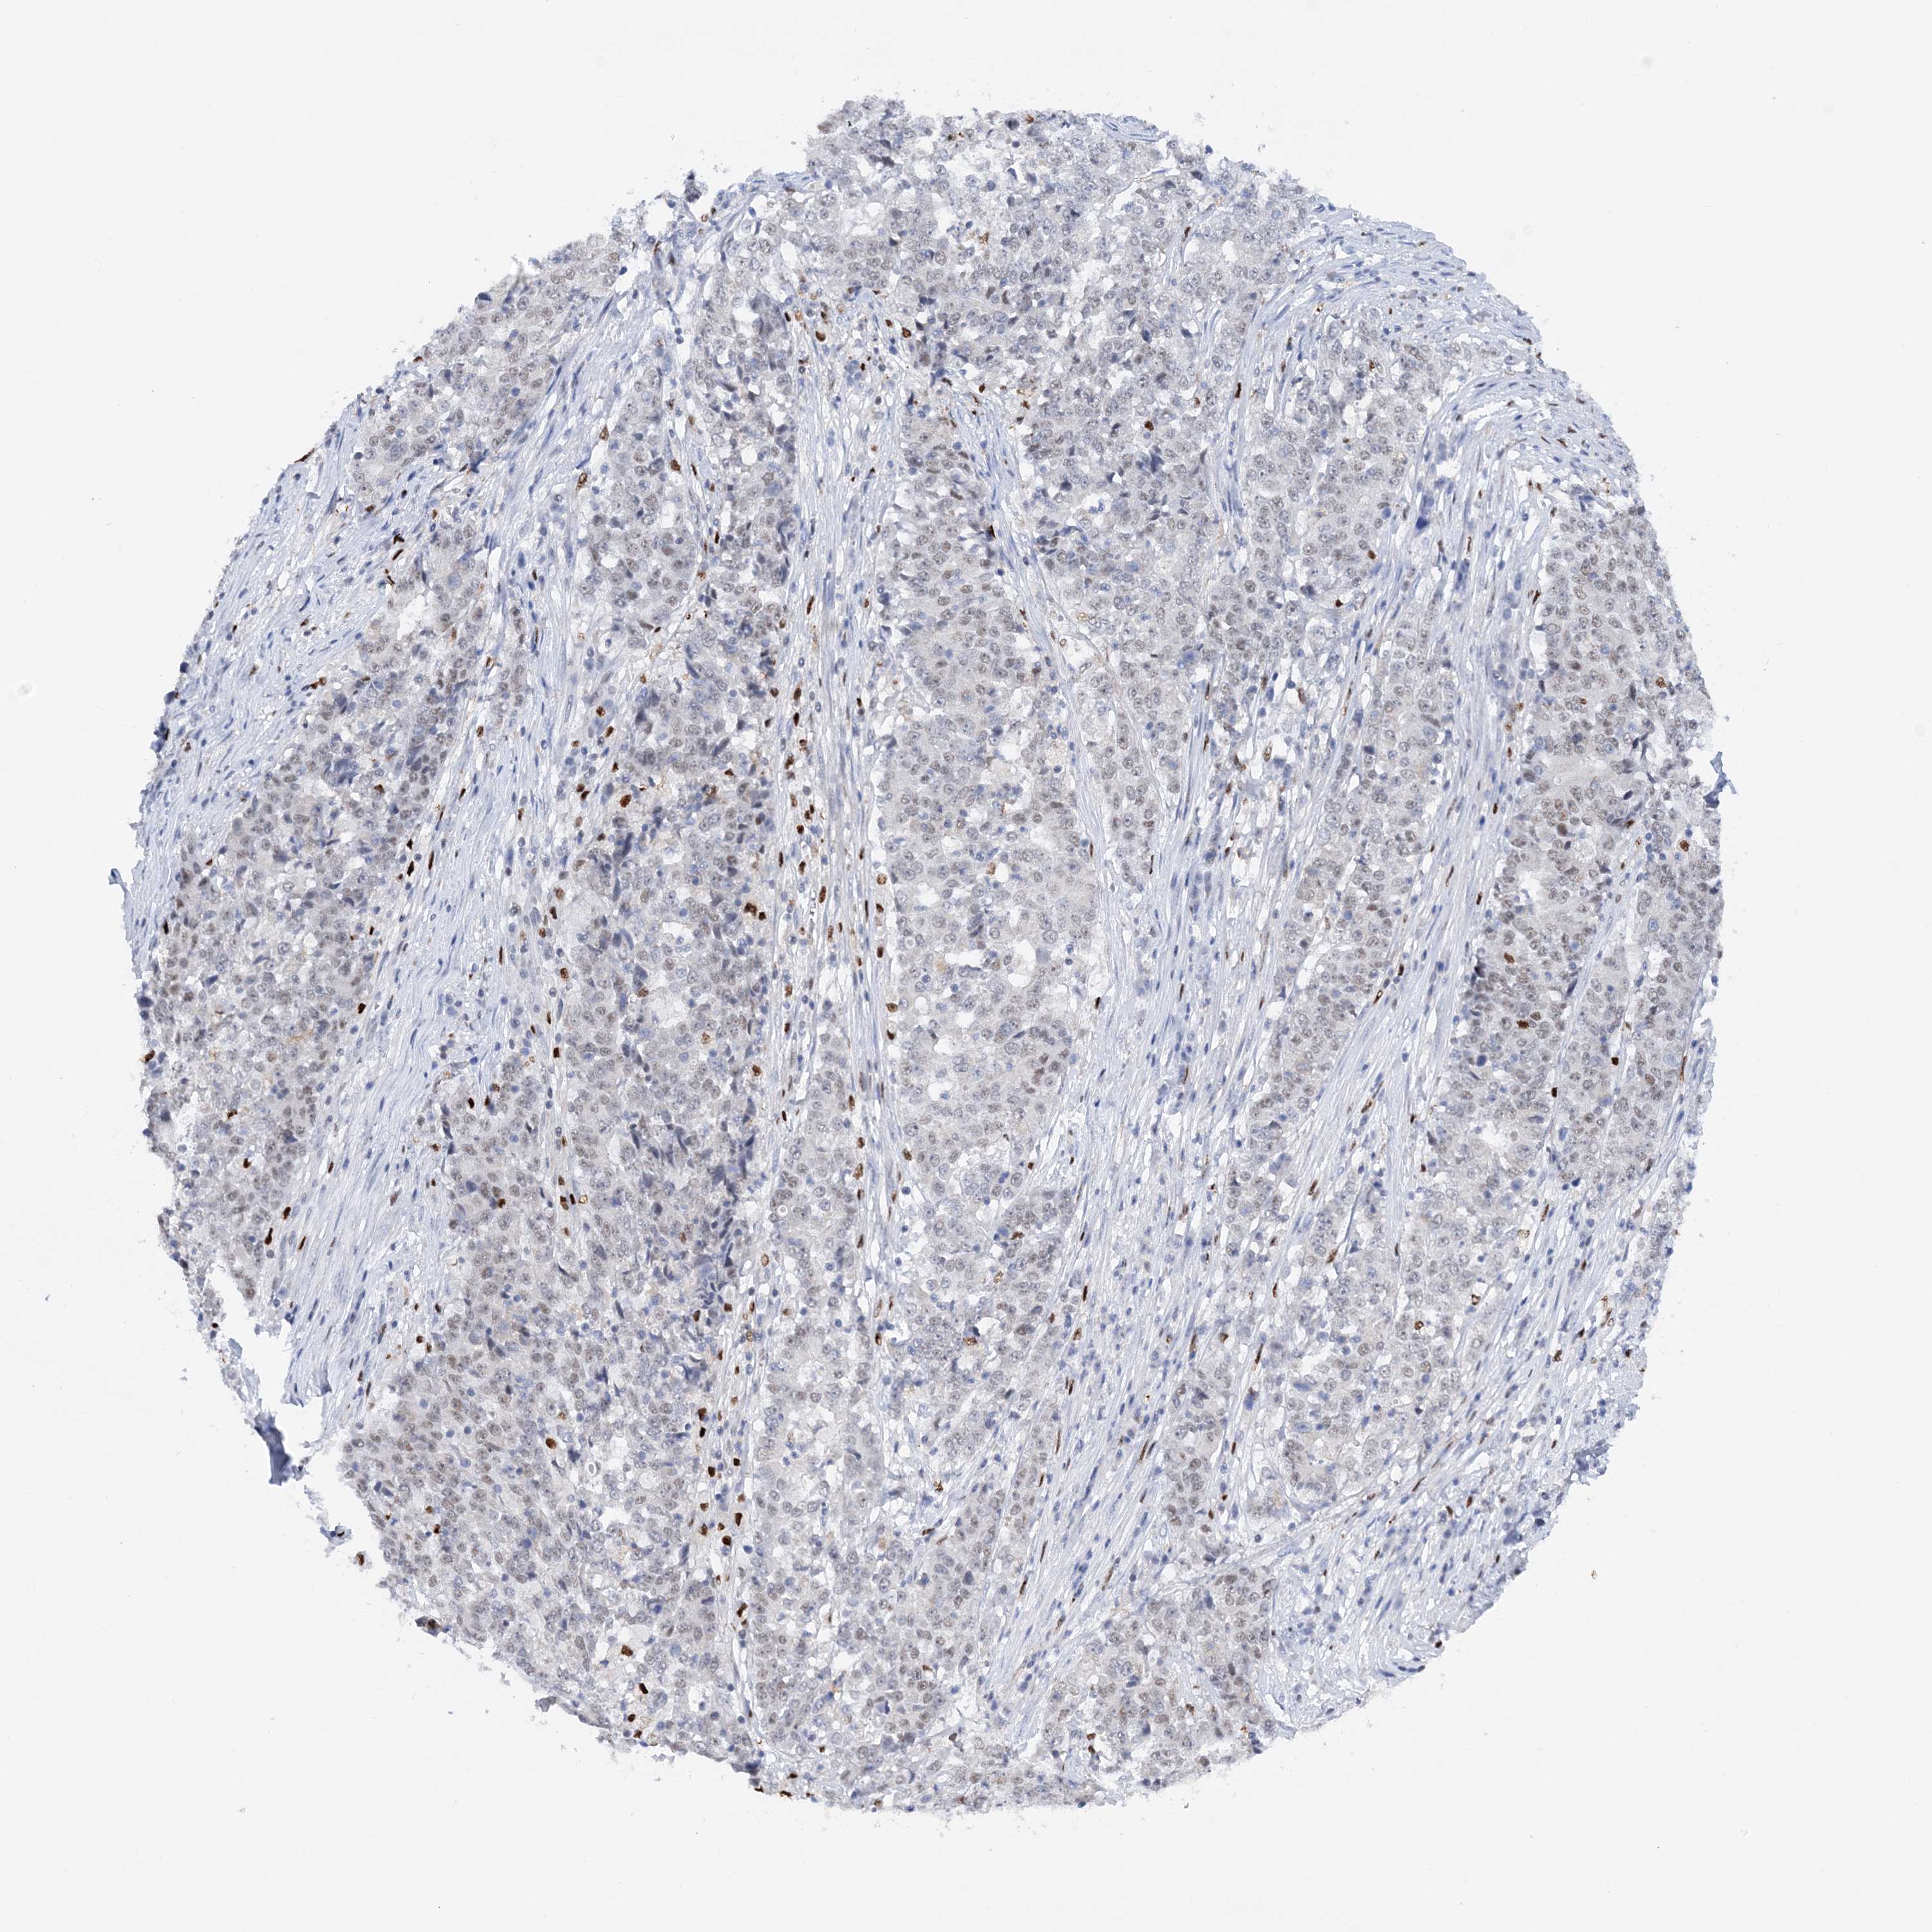

STOMACH CANCER - Protein expressioni

A mouse-over function shows sample information and annotation data. Click on an image to view it in a full screen mode. Samples can be filtered based on level of antibody staining by selecting one or several of the following categories: high, medium, low and not detected. The assay and annotation is described here.

Antibody stainingi

Antibody staining in the annotated cell types in the current human tissue is reported as not detected, low, medium, or high, based on conventional immunohistochemistry profiling in selected tissues. This score is based on the combination of the staining intensity and fraction of stained cells.

Each image is clickable and will lead to virtual microscopy that enables deeper exploration of all samples and also displays staining intensity scores, fraction scores and subcellular localization as well as patient and tissue information for each sample.

Antibody HPA036999

Antibody HPA041289

Staining

High

Medium

Low

Not detected

Intensity

Strong

Moderate

Weak

Negative

Quantity

>75%

75%-25%

<25%

None

Location

Nuclear

Cytoplasmic/membranous

Cytoplasmic/membranous,nuclear

Adenocarcinoma, NOS

Adenocarcinoma, High grade